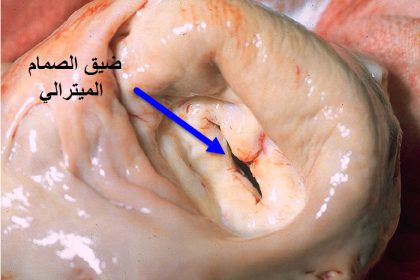

- تضيق الصمامات: يحدث عندما تصبح الصمامات ضيقة، ما يُعيق تدفق الدم. مثال: تضيق الصمام الأبهري.

الفرق بين ارتجاع و ارتخاء الصمام الميترالي | تعرف على أبرز الفروقات

تناولنا من قبل أمراض الصمام الميترالي بشكل مفصل…

جراحه اصلاح الصمام الميترالي

تعتبر جراحه اصلاح الصمام الميترالي هي الحل الامثل…